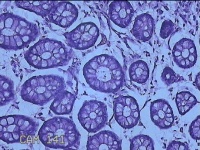

乙状结肠粘膜

性别

男

年龄

52岁

临床诊断

结肠息肉

一般病史

乙状结肠可见息肉

标本名称

大体所见

灰白粉红色组织小米大一团。

自动采图系统很方便,图片采太多没病变的图,几张就够了,而且制片技术急需改进,

有点增生性息肉的感觉